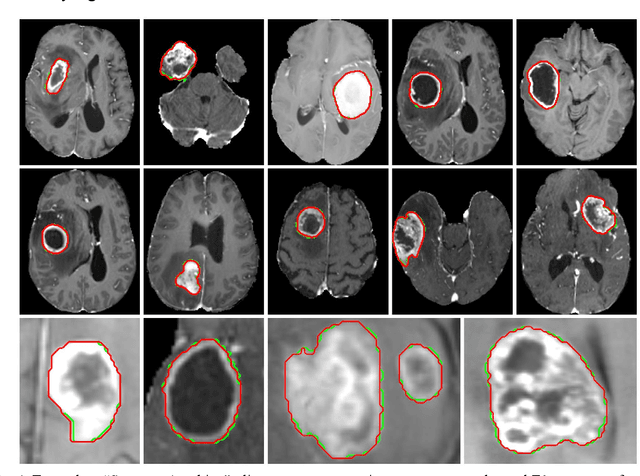

Abstract:Background: Tumor segmentation in MRI is crucial in radiotherapy (RT) treatment planning for brain tumor patients. Segment anything (SA), a novel promptable foundation model for autosegmentation, has shown high accuracy for multiple segmentation tasks but was not evaluated on medical datasets yet. Methods: SA was evaluated in a point-to-mask task for glioma brain tumor autosegmentation on 16744 transversal slices from 369 MRI datasets (BraTS 2020). Up to 9 point prompts were placed per slice. Tumor core (enhancing tumor + necrotic core) was segmented on contrast-enhanced T1w sequences. Out of the 3 masks predicted by SA, accuracy was evaluated for the mask with the highest calculated IoU (oracle mask) and with highest model predicted IoU (suggested mask). In addition to assessing SA on whole MRI slices, SA was also evaluated on images cropped to the tumor (max. 3D extent + 2 cm). Results: Mean best IoU (mbIoU) using oracle mask on full MRI slices was 0.762 (IQR 0.713-0.917). Best 2D mask was achieved after a mean of 6.6 point prompts (IQR 5-9). Segmentation accuracy was significantly better for high- compared to low-grade glioma cases (mbIoU 0.789 vs. 0.668). Accuracy was worse using MRI slices cropped to the tumor (mbIoU 0.759) and was much worse using suggested mask (full slices 0.572). For all experiments, accuracy was low on peripheral slices with few tumor voxels (mbIoU, <300: 0.537 vs. >=300: 0.841). Stacking best oracle segmentations from full axial MRI slices, mean 3D DSC for tumor core was 0.872, which was improved to 0.919 by combining axial, sagittal and coronal masks. Conclusions: The Segment Anything foundation model, while trained on photos, can achieve high zero-shot accuracy for glioma brain tumor segmentation on MRI slices. The results suggest that Segment Anything can accelerate and facilitate RT treatment planning, when properly integrated in a clinical application.